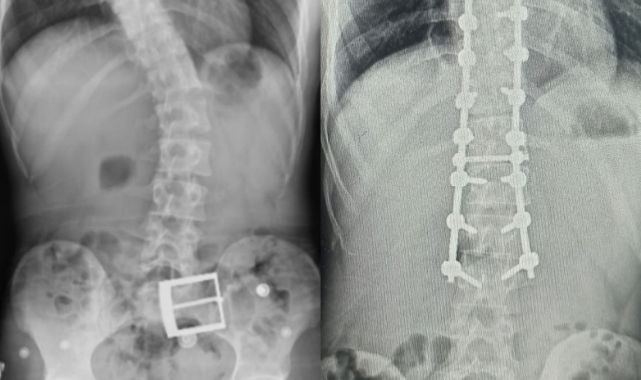

Sırt ağrıları, omurga eğriliği ve kamburlaşması olan 20 yaşındaki hasta Ahmet Akan, Tokat’tan Samsun’a giderek ameliyat oldu. 7 saat süren ameliyat sonunda Ahmet Akan sağlığına kavuştu.

Yapılan muayene ve incelemeler sonucu hastada 73 derece skolyoz (omurga eğriliği) ve kifoz (kamburluk) tespit edilerek Ahmet Akan’a ameliyat önerildi. Samsun Üniversitesi Tıp Fakültesi Ortopedi ve Travmatoloji Anabilim Dalı Öğretim Üyelerinden Dr. Öğr. Üyesi Ömer Bozduman, deneyimli ameliyat ve anestezi ekibi eşliğinde görev yaptığı Samsun Eğitim ve Araştırma Hastanesi’nde 7 saat süren başarılı bir skolyoz ameliyatı gerçekleştirdi.

Hasta ile ilgili bilgi veren Dr. Öğretim Üyesi Ömer Bozduman, “Hastamız artan sırt ağrıları ve omurga eğriliğinin ilerlemesi şikâyetiyle kliniğimize başvurdu. İnceleme ve değerlendirmelerimiz sonucu ameliyat kararı verdik. 7 saat süren skolyoz ameliyatını takiben 12 saat sonra hastamız kaldırılıp yürütüldü. Ameliyat sonrası nörolojik olarak hiçbir sorunu yok. Eğriliği tamamen düzeldi, boyu uzadı. Şu an kendisi yürüyüp gezebiliyor. Hastayı 5 gün sonra taburcu edip evine gönderiyoruz. Her ameliyatta olduğu gibi skolyoz ameliyatlarında da ekip çalışması çok önemlidir. Uzun süren bu ameliyatı, hastanemizin özverili ameliyat ve servis hemşireleri ve deneyimli anestezi ekibi ile gerçekleştirdik” dedi.